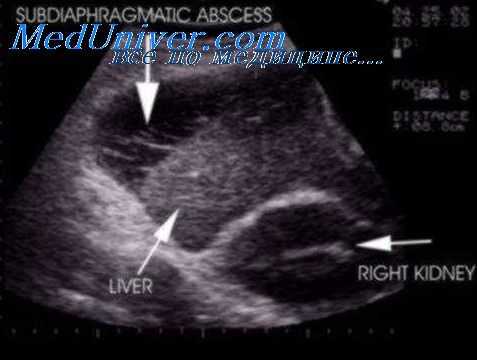

- УЗИ брюшной полости и забрюшинного пространства. Выявляет воспалительные процессы в поджелудочной железе, почках, ретроперитонеальной клетчатке, жидкость в брюшной полости. При большом размере абсцесса удается визуализировать его как округлую гипоэхогенную тень.

МСКТ и УЗИ брюшной полости позволяют подтвердить наличие жидкости, гноя и газа в брюшной или плевральной полости, изменение положения и состояния прилежащих внутренних органов (например, деформацию желудка, смещение продольной оси сердца и др.). Диагностическая пункция абсцесса допустима лишь во время операции.